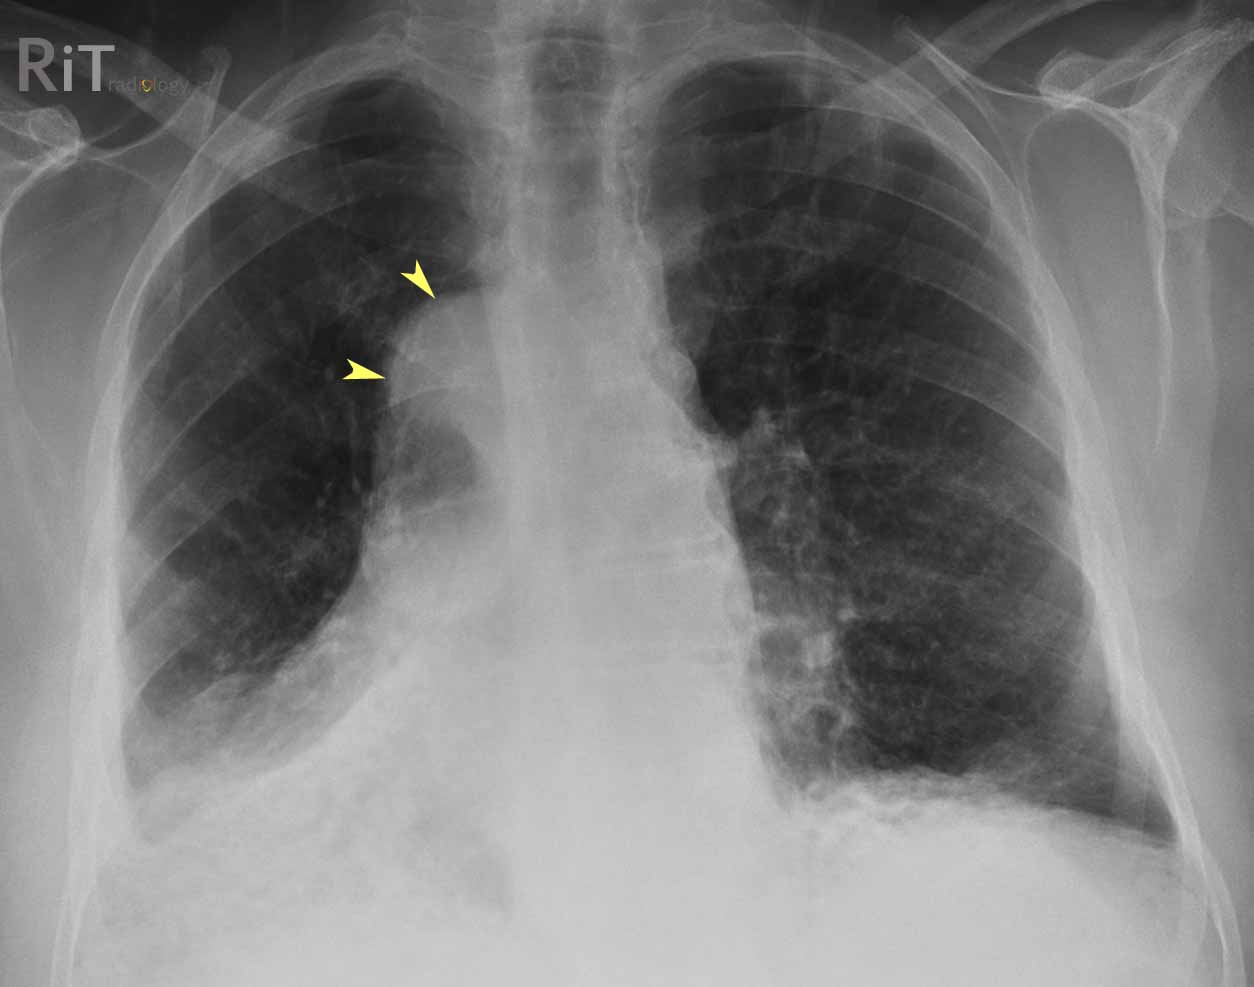

Синдром картагенера у детей

Синдром картагенера у детей 113 фотографий